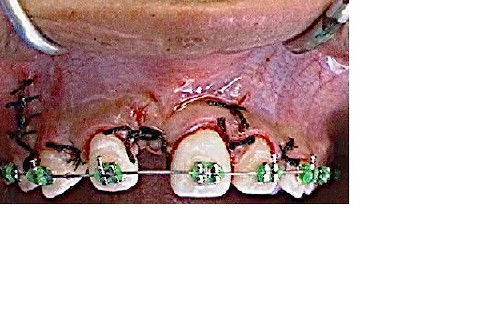

Fotosintra-bucais-iníciodonivelamento.Verifica-seaausênciado11(incluso/impactado).

evidenciação da coroa do 11, para remoção da coroa e porção radicular.

condição imediatamente após a cirurgia;